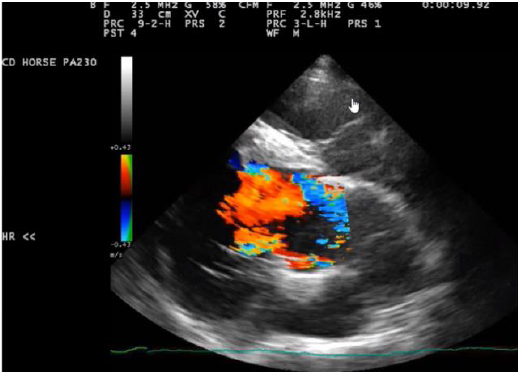

What is seen?

Ventricular defect

Aortic valve insufficiency

A